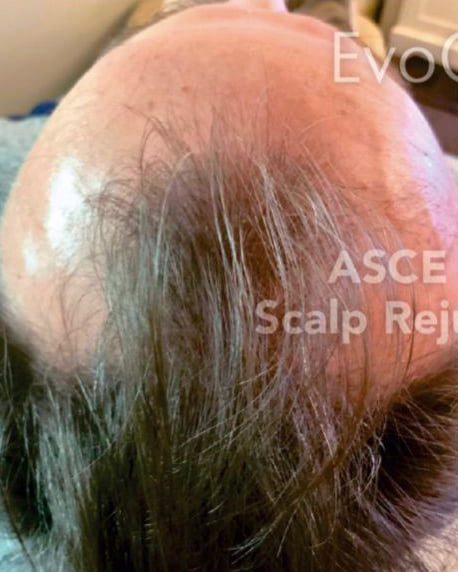

Alopecia Treatment

Before

After

Before

After